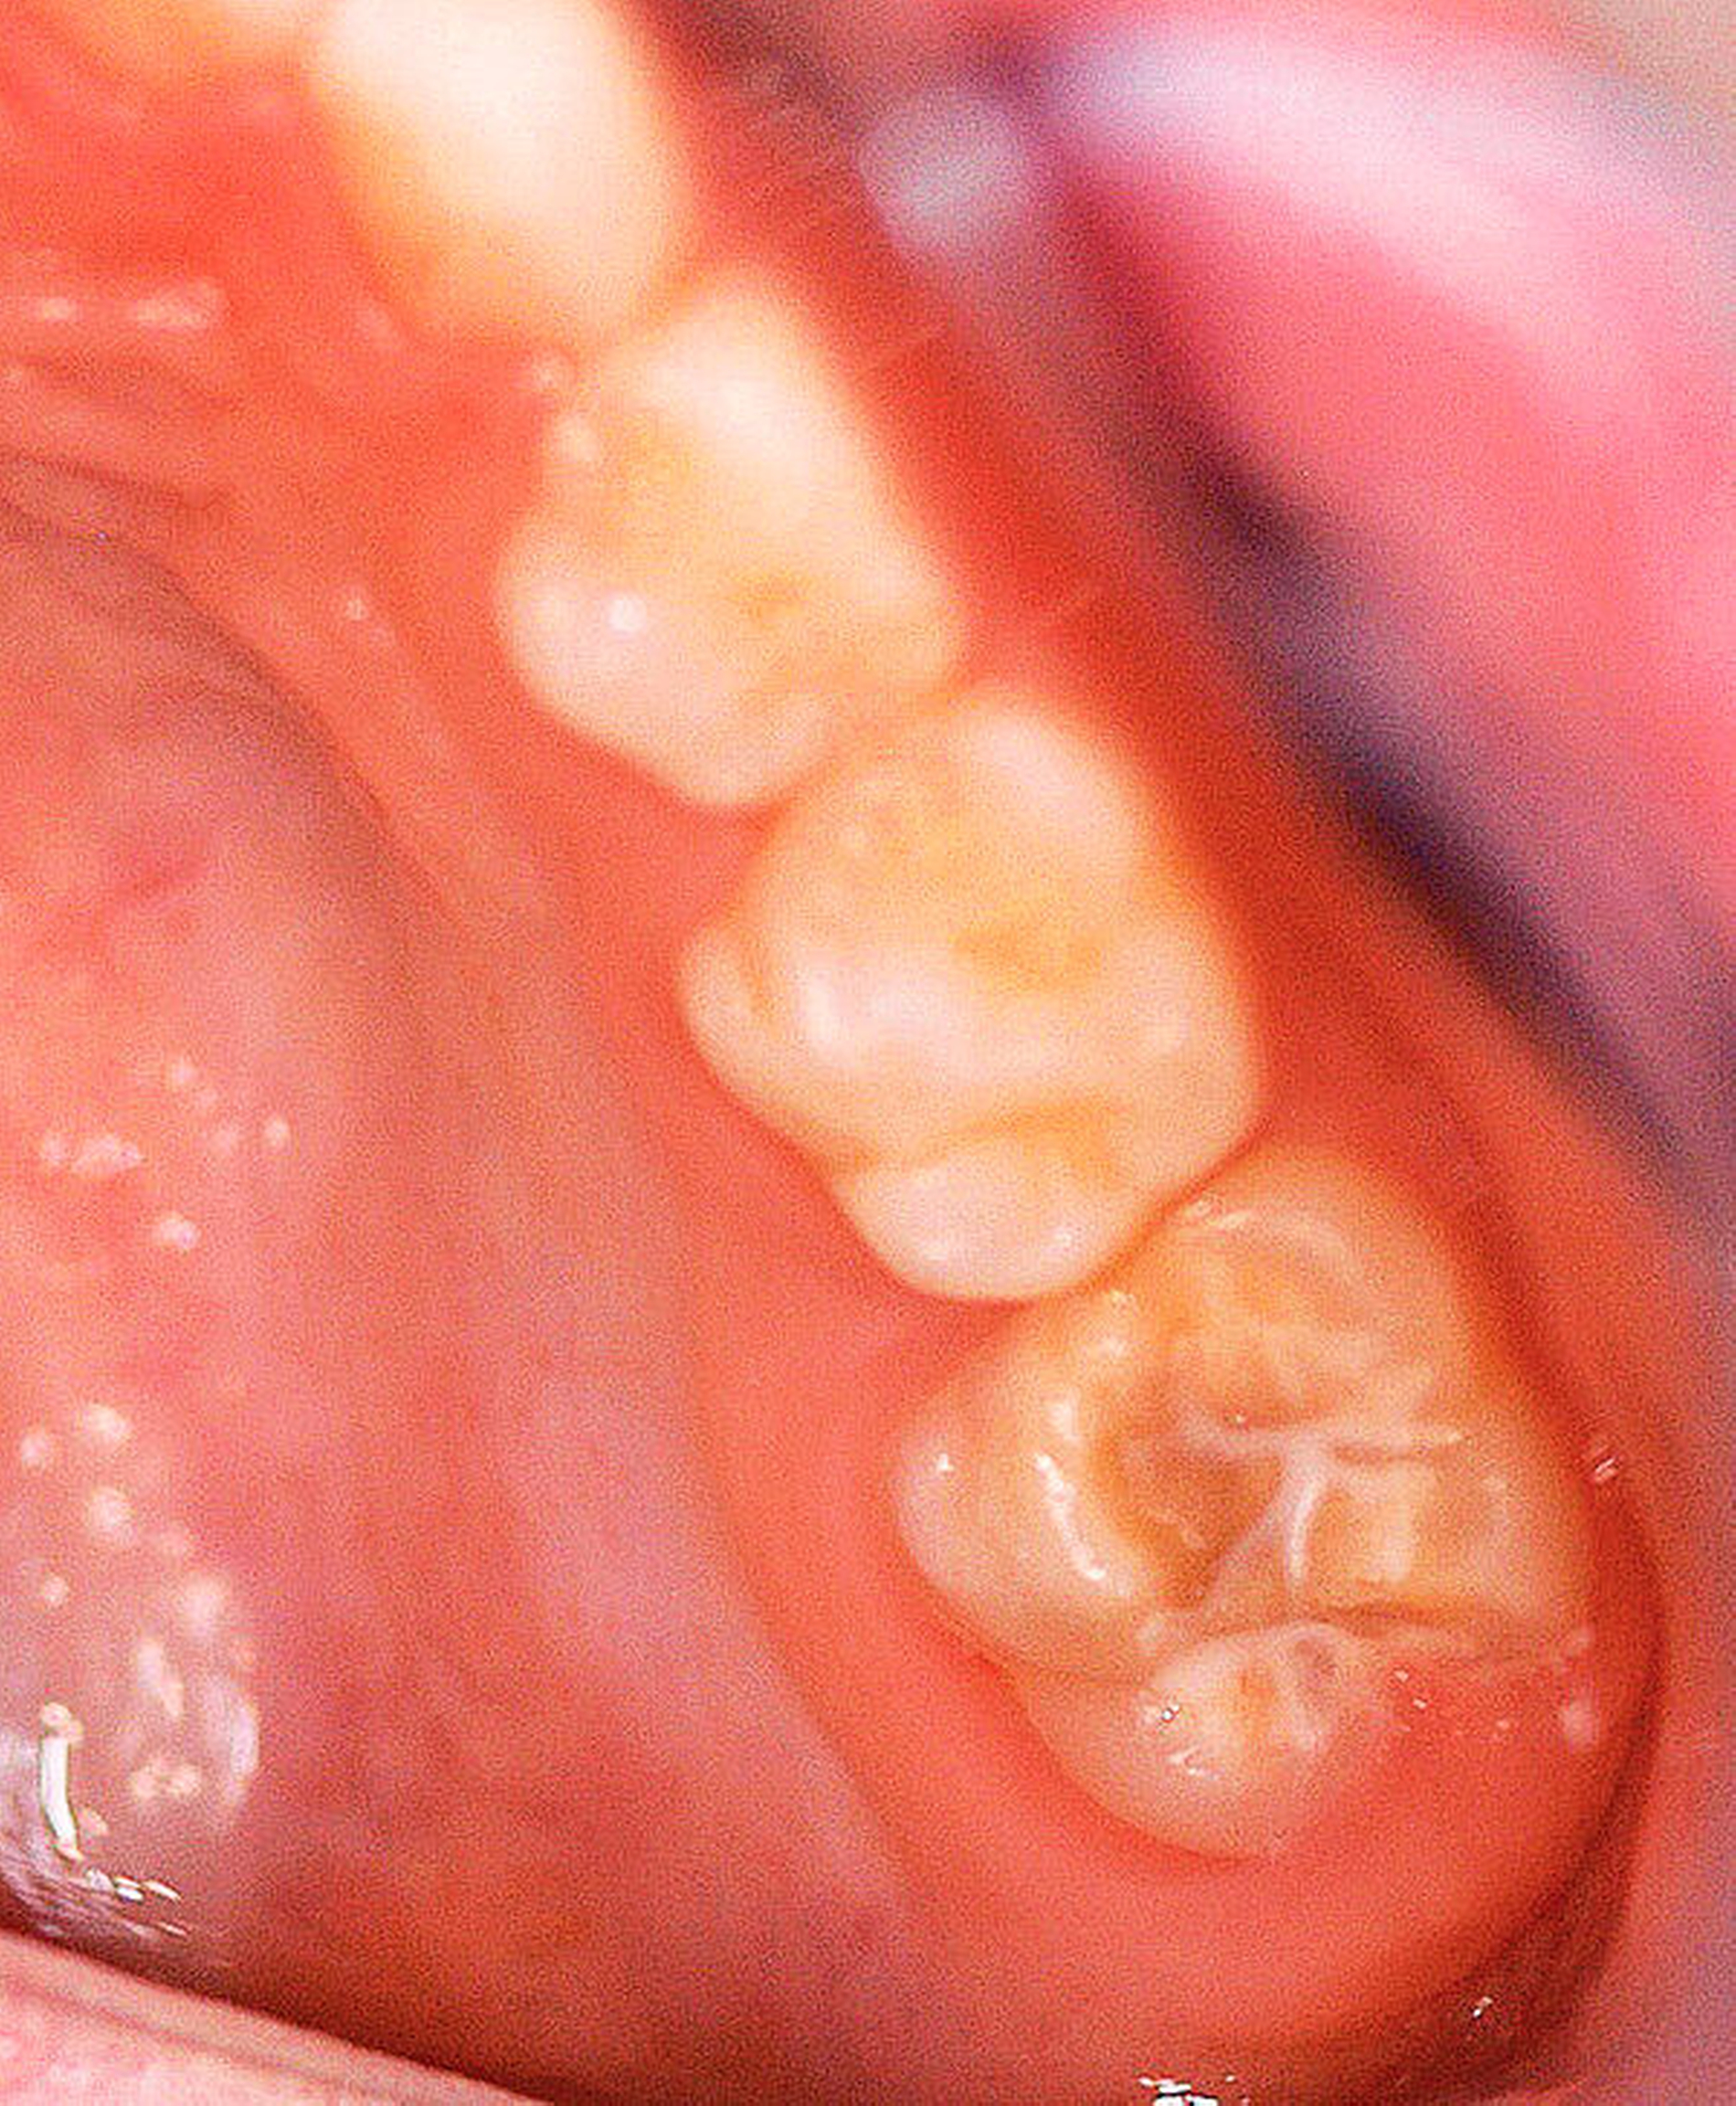

Der Begriff der „Molaren-Inzisiven-Hypomineralisation“ hat vor knapp 20 Jahren Eingang in die Literatur gefunden [Weerheijm et al., 2001]. Beschrieben wird eine systemisch bedingte Hypomineralisation von ein bis vier bleibenden ersten Molaren mit oder ohne Beteiligung der Inzisiven (Abbildungen 1 und 2).

Die Ausprägung der Mindermineralisation kann stark variieren (Abbildungen 3 und 4). Klinisch zeigen sich an den betroffenen Zähnen unterschiedlich starke Verfärbungen beziehungsweise Opazitäten bis hin zu ausgeprägten Schmelzverlusten. So kann die Mineralisationsstörung im Bereich der Molaren auf einzelne Bereiche beschränkt sein, das Fissurenrelief einbeziehen oder sich über die gesamte Glattfläche erstrecken [Koch et al., 1987]. Bei den Inzisiven ist die Mindermineralisation bukkal zu finden. Geringgradig betroffene Zähne sind dabei eher durch weiß-gelbliche oder gelb-braune, unregelmäßige Verfärbungen gekennzeichnet, schwere Hypomineralisationsformen weisen dagegen abgesplitterte oder fehlende Schmelz- und/oder Dentinareale unterschiedlichen Ausmaßes auf.

Bildgruppe Abb. 7–14:Grade des MIH-Treatment-Need-Index im klinischen Erscheinungsbild